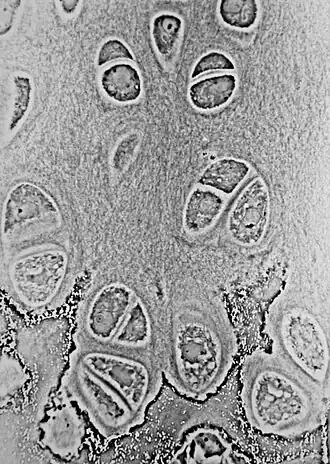

Эпифизарная пластинка участвует в продольном росте костей. Хондроциты пластинки находятся в постоянном митотическом делении. Дочерние клетки собираются со стороны эпифиза, материнские оттесняются к метафизу. На фоне дегенерации старых хондроцитов остеобласты формируют новую костную ткань. В конце полового созревания эпифизарные хрящевые клетки прекращают деление, и вся хрящевая ткань постепенно замещается костной, за исключением тонкой эпифизарной линии[1].

Хрящевая пластинка роста имеет специфическую зональную организацию. Различают относительно неактивную резервную зону (эпифизарный конец), пролиферативную зону, гипертрофическую зону и зону оссифицирующегося хряща (метафиз).